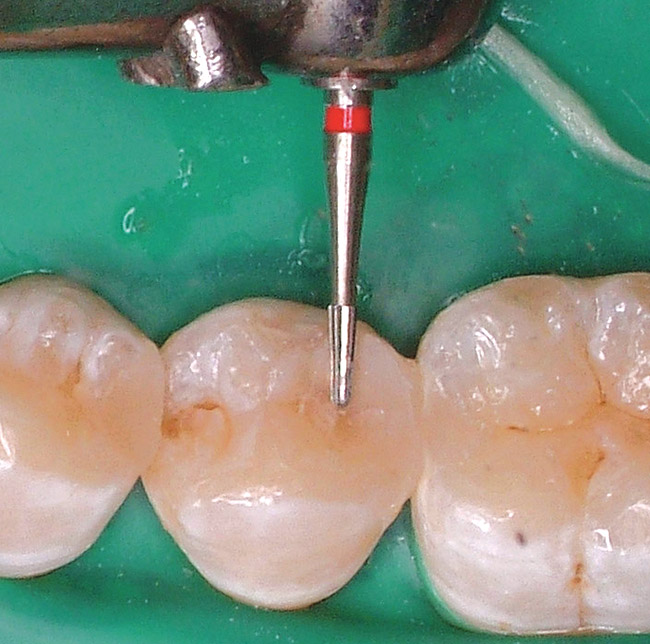

Finishing and polishing posterior composite resin restorations follow the same principles as those for anterior composite resin restorations, with one exception. Because these restorations are not in the esthetic zone (ie, do not need to be highly lustrous when dry), they can be polished to a smooth finish that is indistinguishable to the patient from the tooth being restored when the patient rubs his or her tongue over the tooth/restoration surface. The restoration is smooth, but not shiny. For example, Figure 8 shows distal caries in a mandibular premolar. Once restored, the restoration will need to be finished and polished. As with anterior composite resin restorations, use a finishing bur (Figure 9) or ultrafine finishing diamond to marginate and shape the restoration. Then polish the surface of the restoration with either composite resin rubber (silicone) polishers (Figure 10) or specialized polishing brushes (Figure 11). A new generation of abrasive-impregnated polishing brushes is available in a variety of shapes and sizes that can be used for almost every posterior composite resin surface. These new brushes have become the composite polishers in these authors' armmentaria. Using these brushes in a right-angle-latch handpiece leaves no mess after finishing and polishing in one step. Even without creating a high luster, this finishing sequence produces a completed restoration with a high esthetic appeal (Figure 12). As with any posterior restoration, after finishing and polishing, the clinician must verify and adjust any occlusal discrepancies.

Figure 9  Gross finishing and marginating of the occlusal surface of a posterior composite resin restoration with an 8-bladed finishing bur (Brasseler USA).

Figure 9